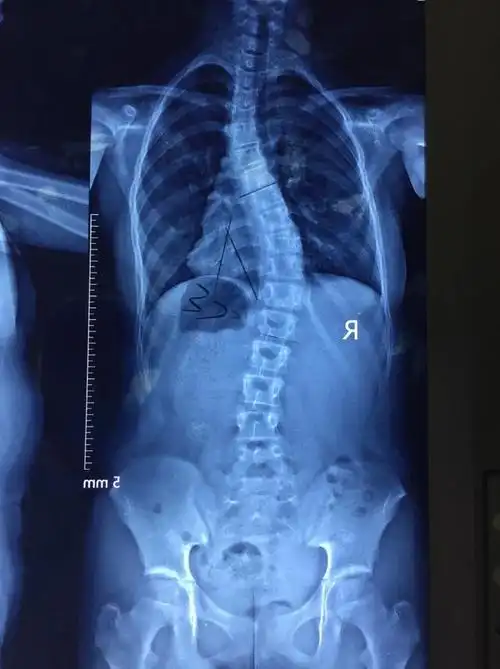

脊柱侧弯

脊柱侧弯最难矫正曲线病例分享